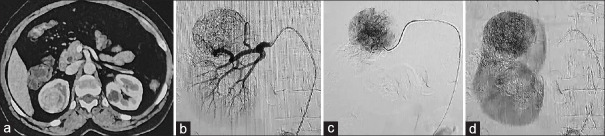

采用一种新颖的方法,利用吲吲吲胺绿荧光进行肾保留手术(NSS),治疗了两个复杂的小肾肿块,克服了目前效果持续时间短和肿瘤不增强的局限性。用二碘化油乳化染料,并在手术当天早晨使用超选择性插管直接肿瘤血供给药。荧光可以在整个手术过程中使用,而无需动脉夹紧,可以快速识别肿瘤,标记边缘,并在去核检查中进行近去核。这种新方法有可能在NSS的各个关键步骤中帮助外科医生。

Two complex small renal masses were operated using a novel method of utilising indocyanine green fluorescence for nephron-sparing surgery (NSS), overcoming its current limitations of short duration of effect and non-enhancement of the tumor. The dye was emulsified with ethiodized oil and a 1:1 mixture was administered on the morning of the surgery using superselective cannulation of the direct tumoral blood supply. The fluorescence could be used throughout the entire course of the surgery irrespective of arterial clamping, allowing quick tumor identification, edge marking, and near-enucleation over enucleoresection. This novel method has the potential to aid the surgeon during various critical steps of NSS.